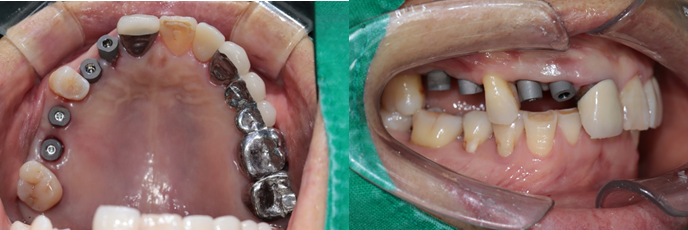

전치부는 지르코니아, 구치부는 보험임플란트 pfm 으로 제작 (70세 여자)

c.c: 앞니가 부러졌고, 오른쪽 어금니가 아파요.